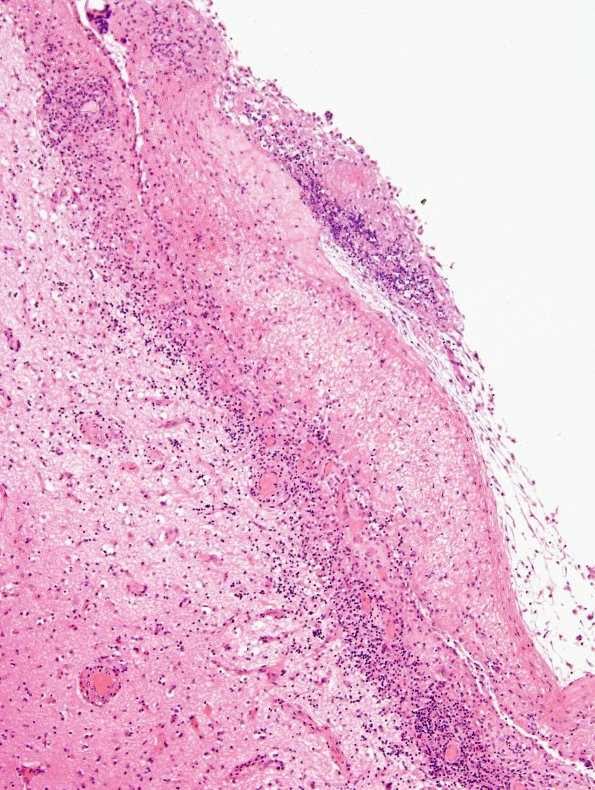

Washington University Experience | INFECTION | Fungus | Candida | 5B2 Fungal Ventriculitis (Case 5) N15 H&E 2

5B2,3 This area shows a mixed inflammatory infiltrate, seen at higher magnification in 5B3 in which the fungal organisms are essentially invisible (H&E)